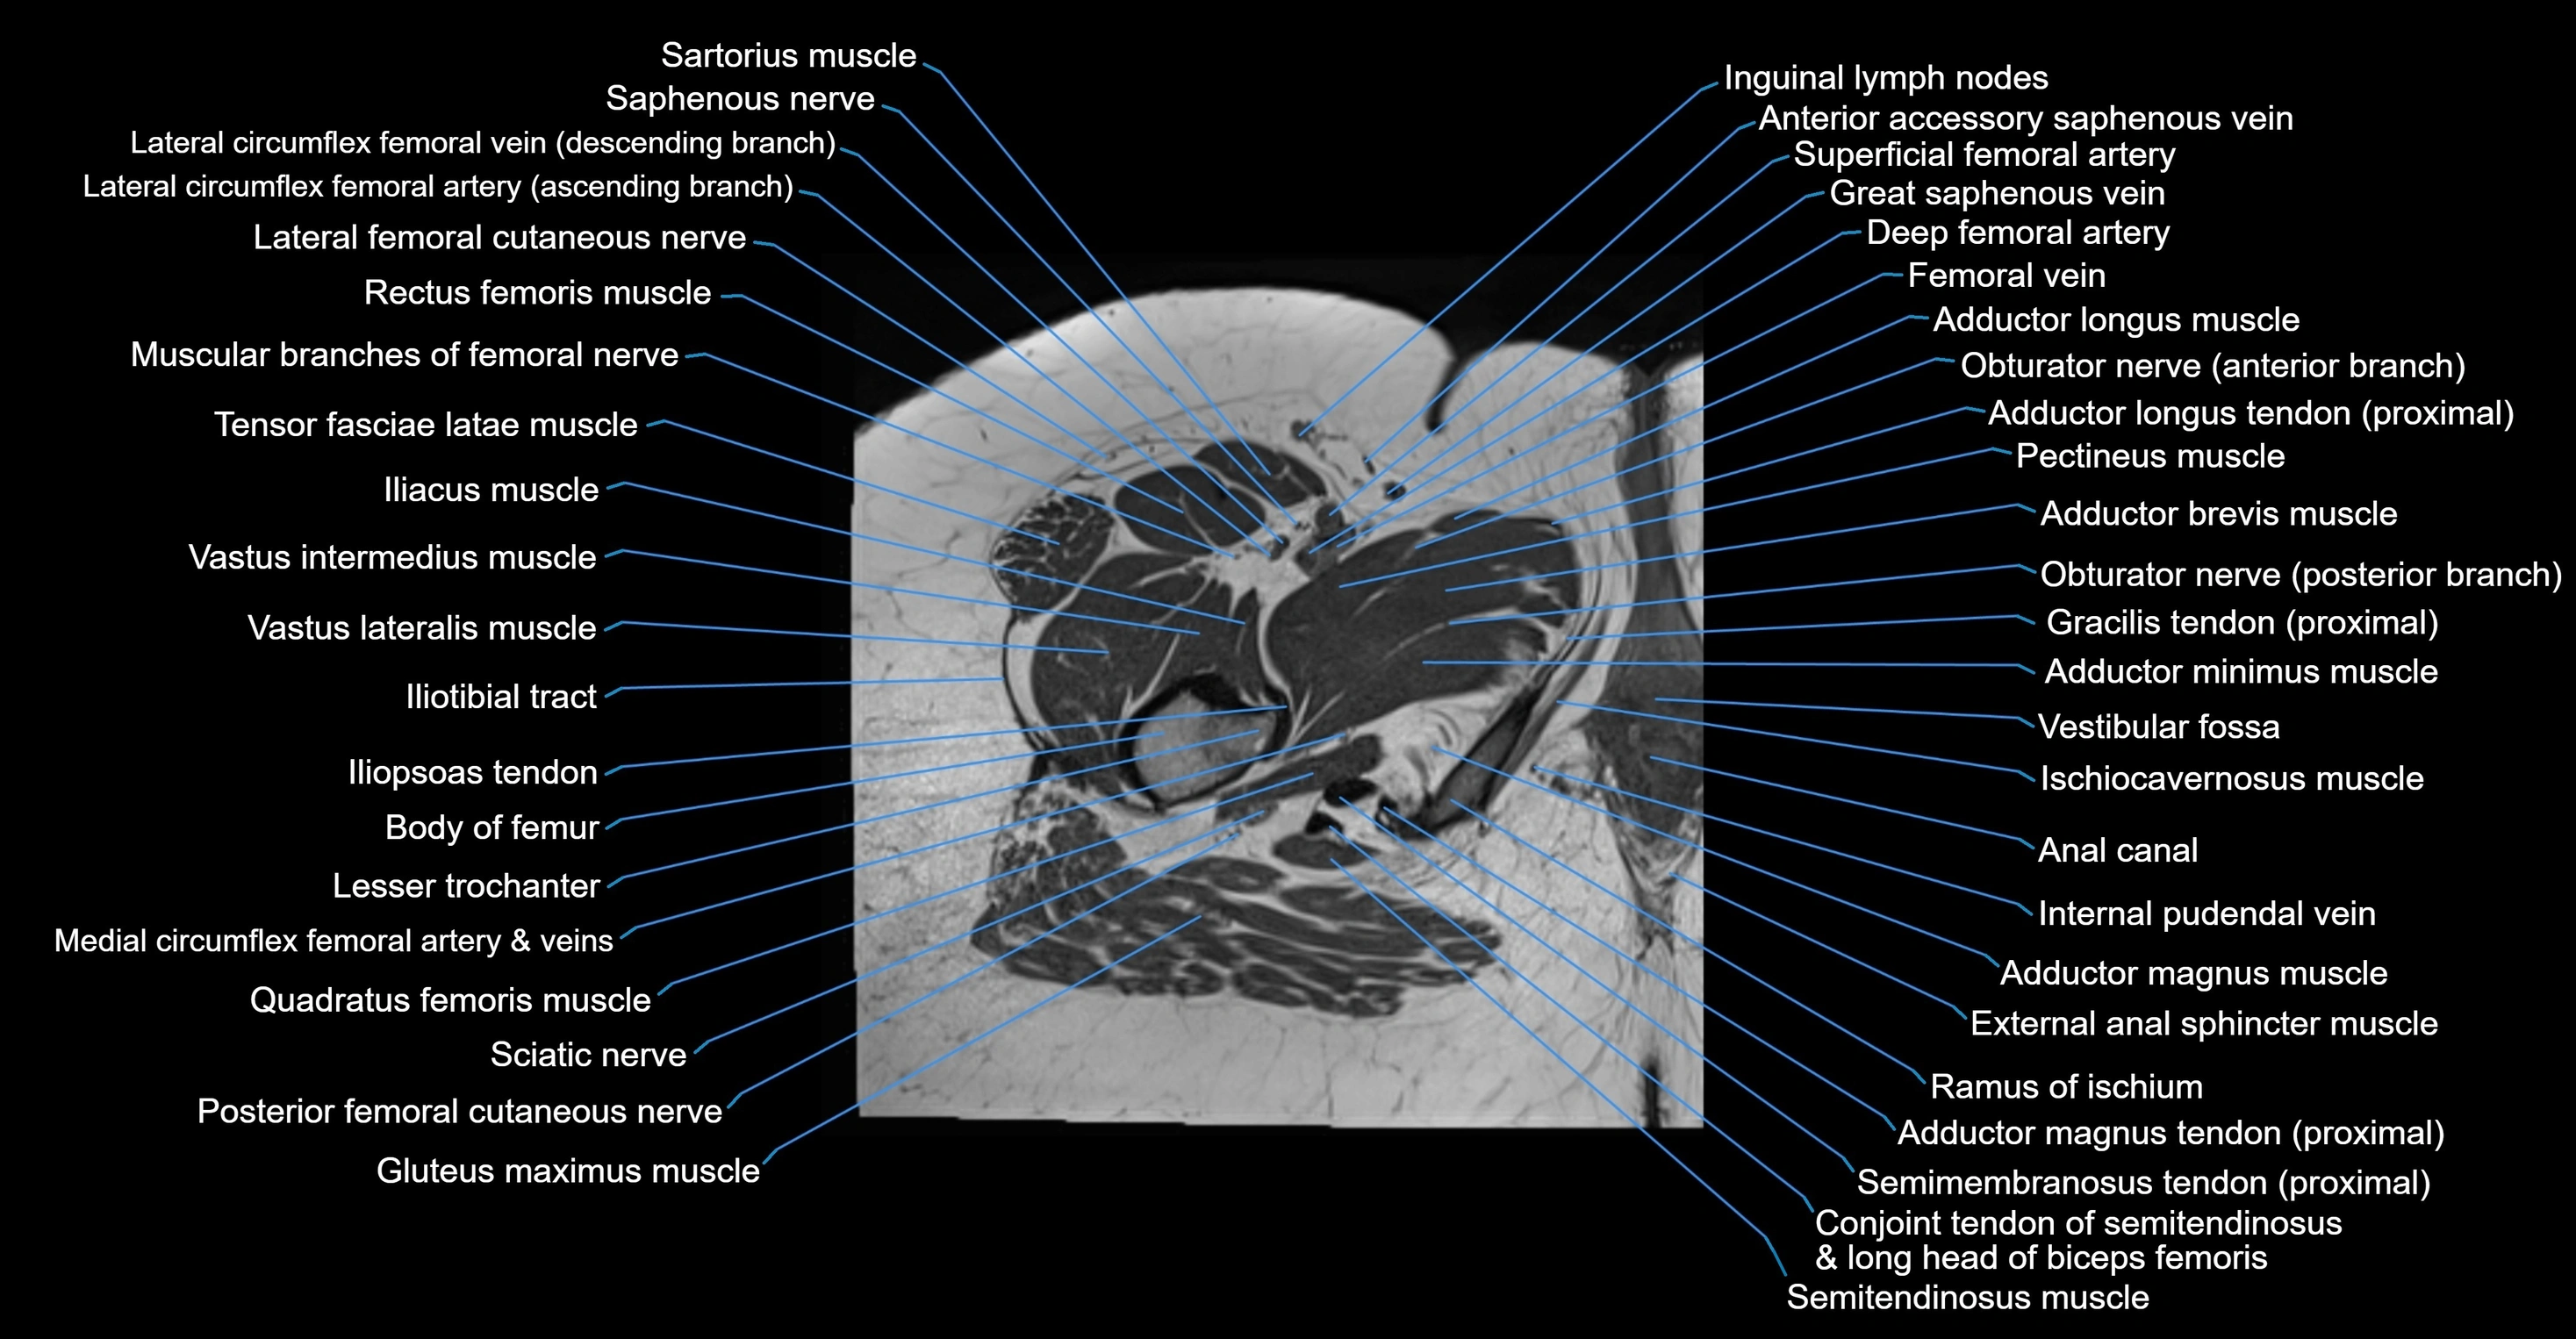

- Adductor brevis muscle

- Adductor longus muscle

- Adductor magnus muscle

- Adductor minimus muscle

- Body of femur

- Conjoint tendon of biceps femoris & semitendinosus

- Gracilis muscle

- Iliopsoas muscle

- Iliopsoas tendon

- Iliotibial tract

- Inferior gemellus muscle

- Lateral femoral cutaneous nerve

- Lesser trochanter

- Medial circumflex femoral artery

- Obturator nerve

- Pectineus muscle

- Posterior femoral cutaneous nerve

- Quadratus femoris muscle

- Rectus femoris muscle

- Sartorius muscle

- Semimembranosus tendon (proximal)

- Tensor fasciae latae muscle

- Vastus intermedius muscle

- Vastus lateralis muscle

- Vastus medialis muscle